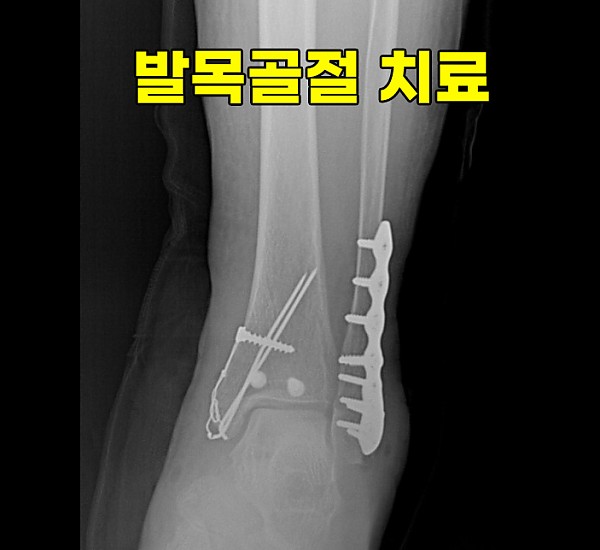

이런 경우에는 수술을 통해서 뼈를 모두

제자리에 맞춰주어야 합니다.

뼈를 맞춘후에는 금속판을 덧대고

나사를 박아서 고정을 해주는 것이죠.